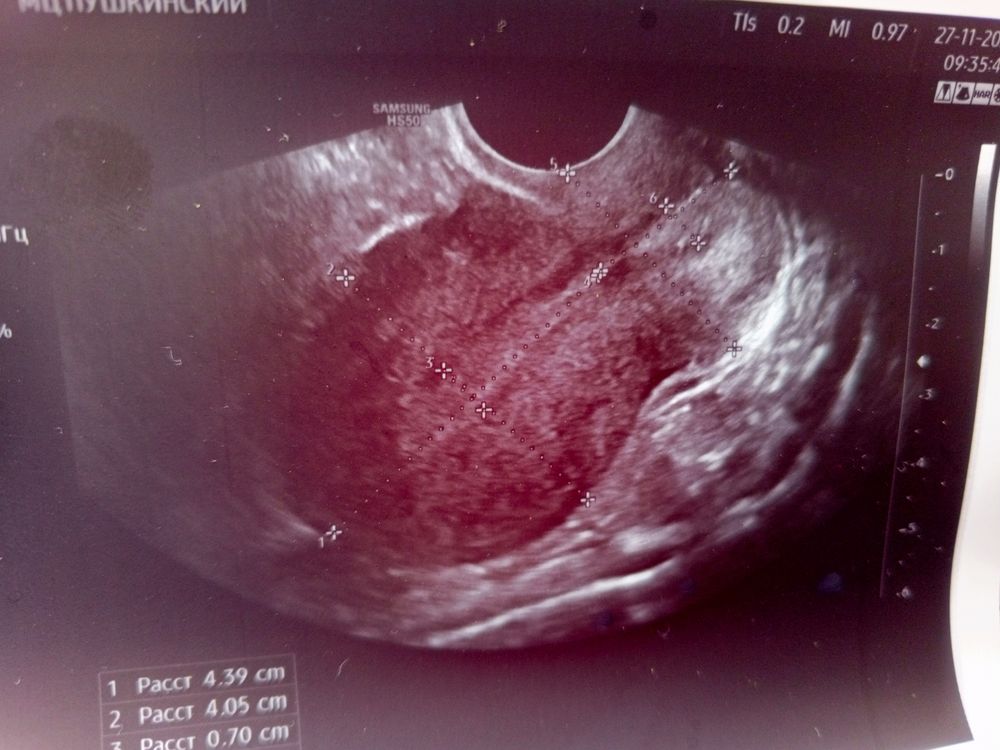

Фолликуламитрию на 13 дц

Первое узи Киста в сосудистом сплетении